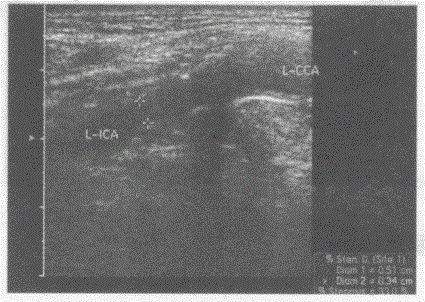

问题 临床资料:男,79岁,自述夜间如厕时出现一过性眼前发黑、摔倒,急诊入院。患高血压、冠心病十余年。头颅CT:双侧基底结区腔隙性脑梗塞。 超声综合描述:双颈总、颈内动脉内膜粗糙,连续中断,中内膜回声强弱不均、增厚,左颈内动脉起始段可见多个中等回声及强回声光团,该段残余管腔内径0.34cm,其远心端管腔内径0.5cm,CDFI:左颈内动脉起始段中等回声及强回声光团区血流充盈缺损,PW:该段V2.06m/s。见下彩图。 {图2} 超声提示:

选项 A.颈动脉正常声像图 B.双侧颈动脉粥样硬化 C.双侧颈动脉粥样硬化并软斑形成 D.双侧颈动脉粥样硬化并左颈内动脉起始段软斑、钙化斑形成并节段性管腔狭窄

答案 D